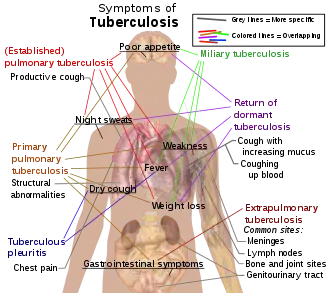

In 2018, one quarter of the world's population was thought to have a latent infection of TB.[6] New infections occur in about 1% of the population each year.[11] In 2022, an estimated 10.6 million people developed active TB, resulting in 1.3 million deaths, making it the second leading cause of death from an infectious disease after COVID-19.[12] As of 2018, most TB cases occurred in the regions of South-East Asia (44%), Africa (24%), and the Western Pacific (18%), with more than 50% of cases being diagnosed in seven countries: India (27%), China (9%), Indonesia (8%), the Philippines (6%), Pakistan (6%), Nigeria (4%), and Bangladesh (4%).[13] By 2021, the number of new cases each year was decreasing by around 2% annually.[12][1] About 80% of people in many Asian and African countries test positive, while 5–10% of people in the United States test positive via the tuberculin test.[14] Tuberculosis has been present in humans since ancient times.[15]

Epidemiology

Roughly one-quarter of the world's population has been infected with M. tuberculosis,[6] with new infections occurring in about 1% of the population each year.[11] However, most infections with M. tuberculosis do not cause disease,[130] and 90–95% of infections remain asymptomatic.[56] In 2012, an estimated 8.6 million chronic cases were active.[131] In 2010, 8.8 million new cases of tuberculosis were diagnosed, and 1.20–1.45 million deaths occurred (most of these occurring in developing countries).[47][132] Of these, about 0.35 million occur in those also infected with HIV.[133] In 2018, tuberculosis was the leading cause of death worldwide from a single infectious agent.[134] The total number of tuberculosis cases has been decreasing since 2005, while new cases have decreased since 2002.[47]

In 2010, rates per 100,000 people in different areas of the world were: globally 178, Africa 332, the Americas 36, Eastern Mediterranean 173, Europe 63, Southeast Asia 278, and Western Pacific 139.[133]